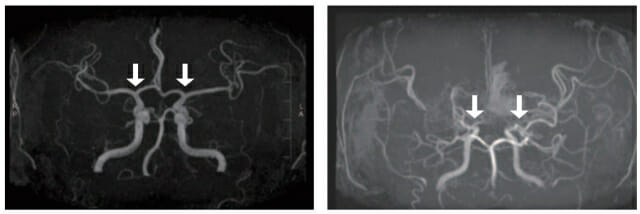

모야모야병은 뇌로 혈액을 공급하는 혈관이 원인 없이 점차 좁아지는 만성 진행성 뇌혈관질환이다. 10세 전후 소아와 40세 전후 성인에서 주로 발병한다. 부작용은 뇌혈관이 막히거나 파열되는 허혈성·출혈성 뇌졸중이 있다. 이 가운데 소아 환자는 성인보다 허혈성 뇌졸중이 빈번하다. 장기 예후는 대체로 양호하지만 3세 미만에서는 진행이 빠르다.